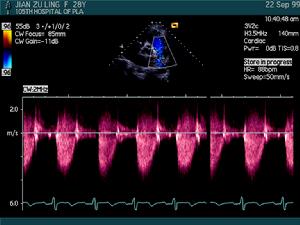

主動脈瓣狹窄超聲心動圖(三)超聲心動圖檢查 M型超聲可見主動脈瓣變厚,活動幅度減小,開放幅度小於18mm,瓣葉反射光點增強提示瓣膜鈣化。主動脈根部擴張,左心室後壁和室間隔對稱性肥厚。二維超聲心動圖上可見主動脈瓣收縮期呈向心性彎形運動,並能明確先天性瓣膜畸形。都卜勒超聲顯示緩慢而漸減的血流通過主動脈瓣,並可計算最大跨瓣壓力階差。